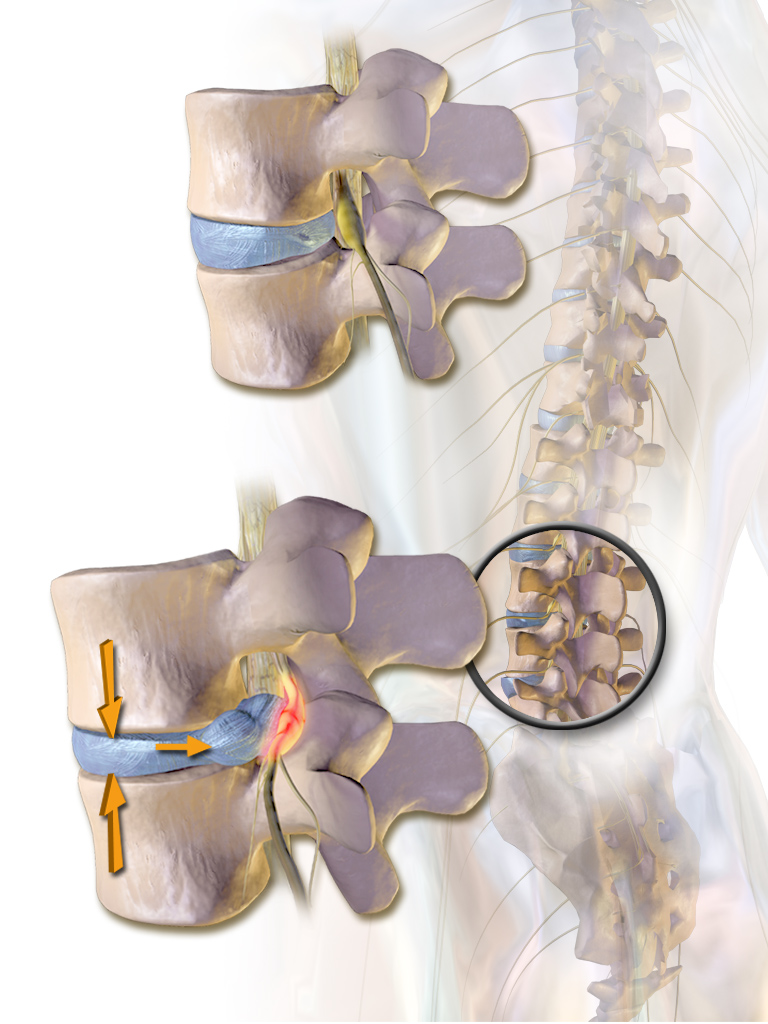

best Slipped disc treatment in Dwarka